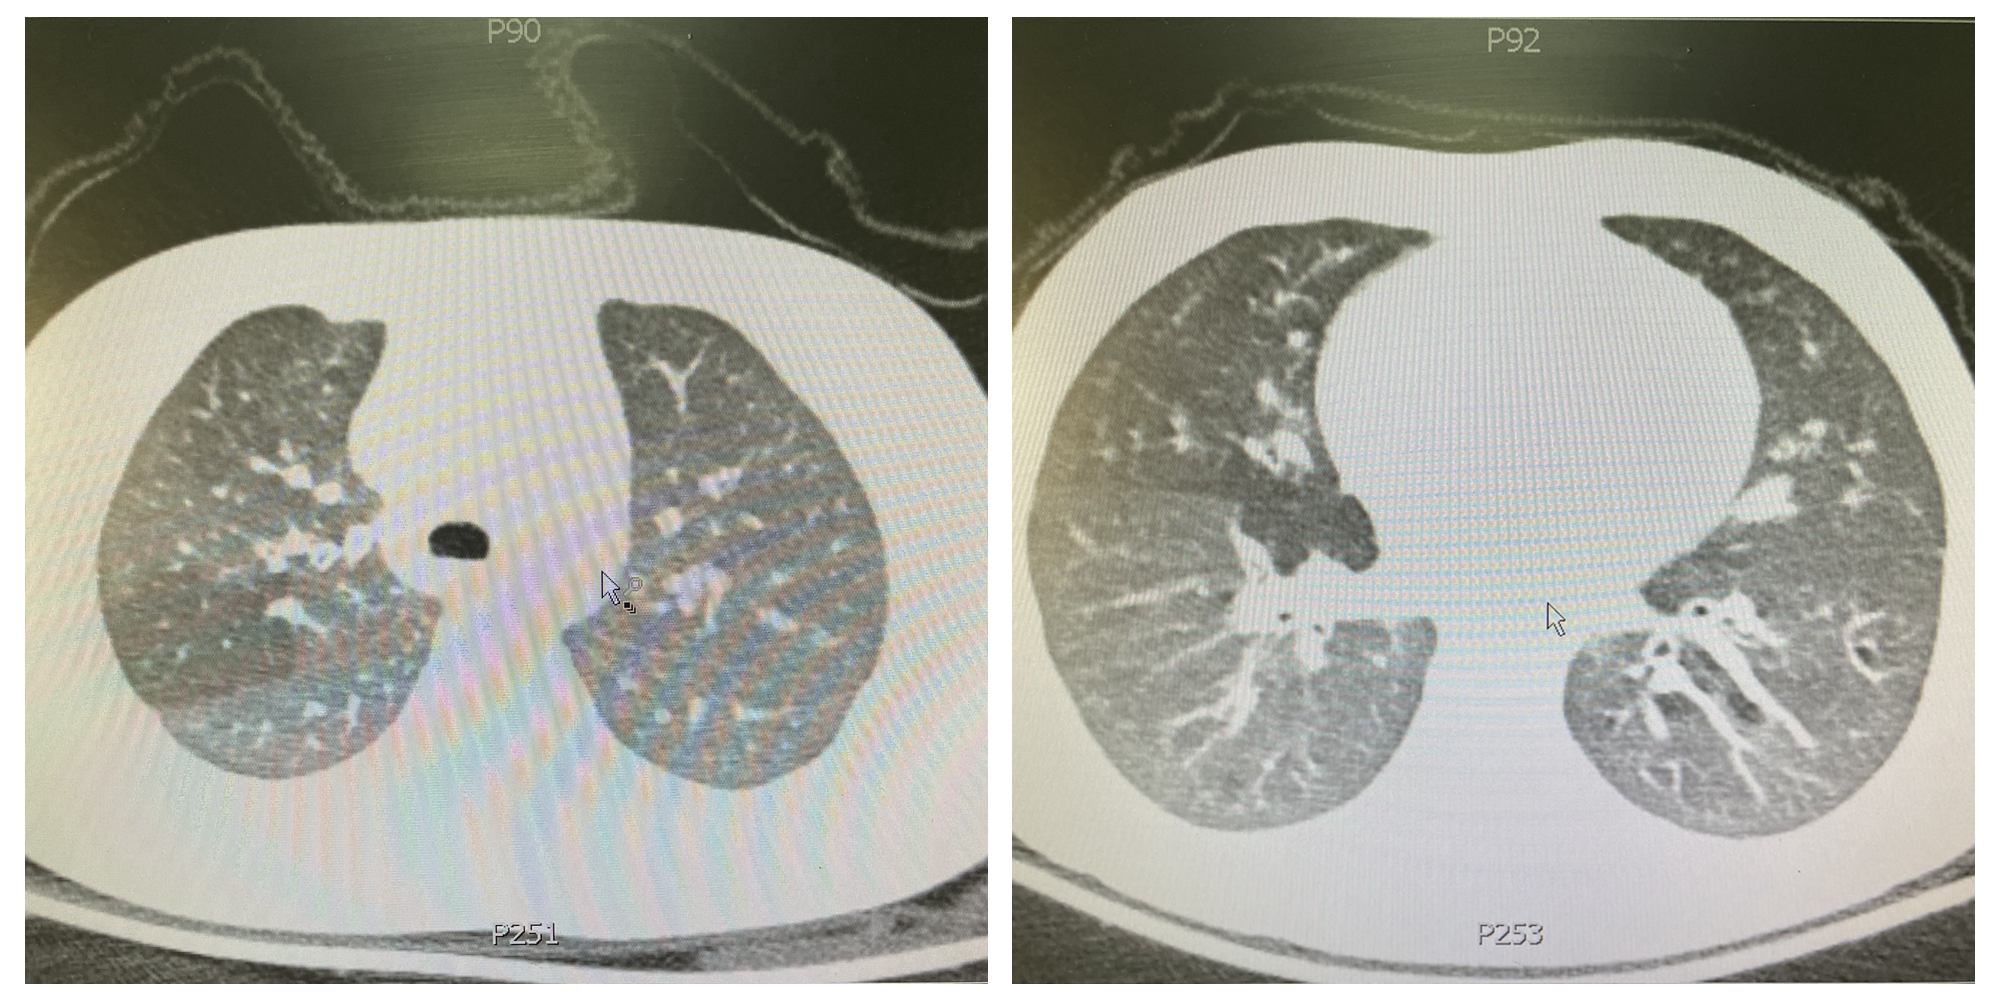

在小可的胸部CT上,我们发现了明显的支气管壁增厚和充气不均匀的表现。“小可没有反复哮喘发作和重度哮喘发作的病史”,罗志娟主任提醒大家到:“这不好解释胸部CT为什么会有只有“重症哮喘”病人才会出现的影像学变化。”